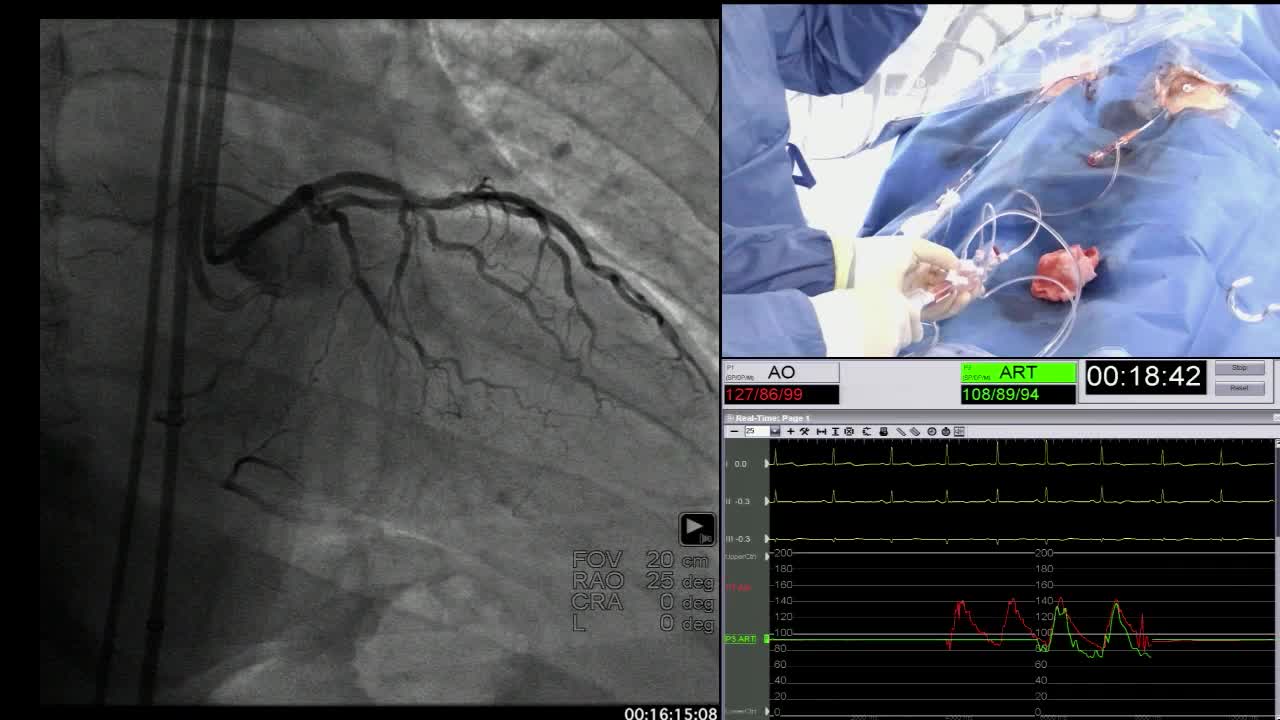

Case 1 - Antegrade Wire